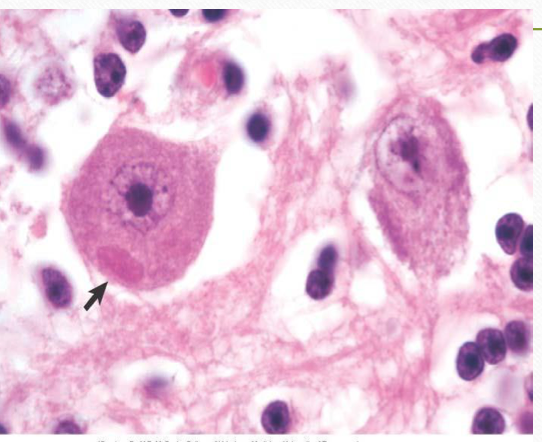

Rabies

negri inclusion bodies